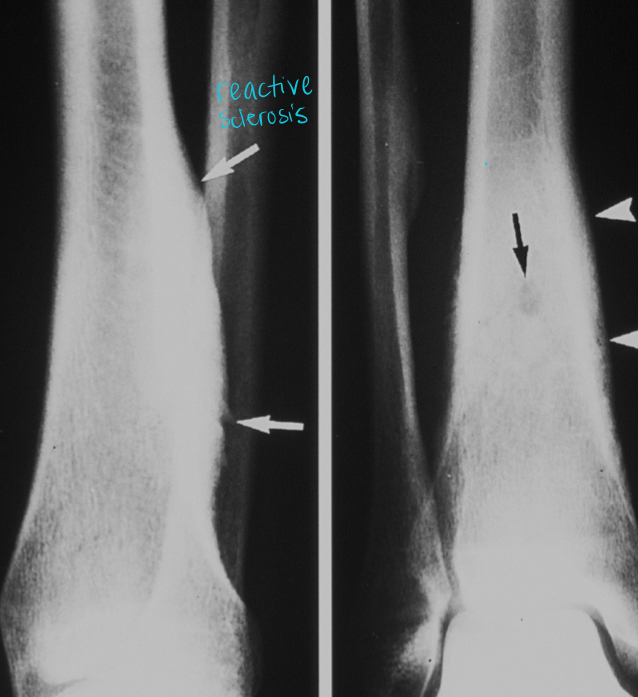

what is this?

typical age?

osteoid osteoma

10-25 yo